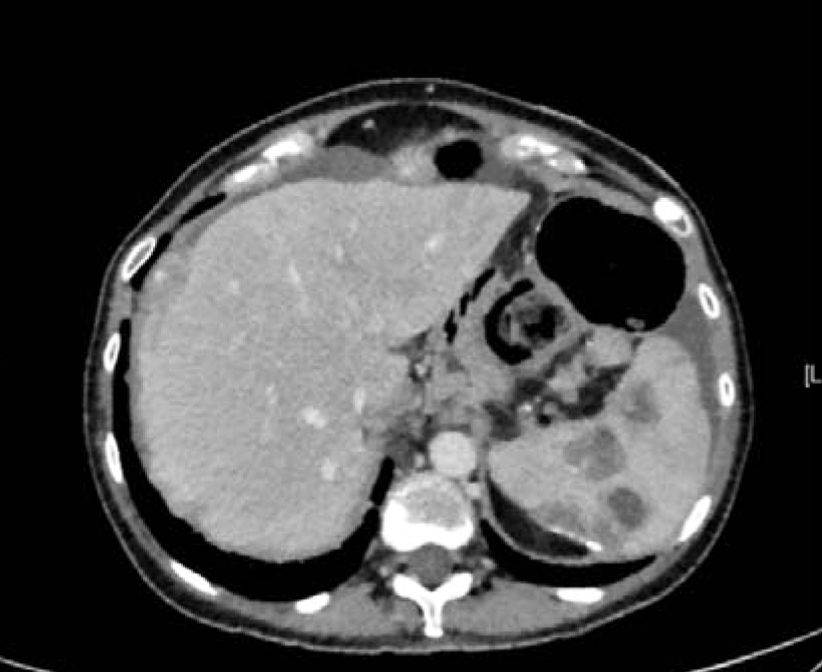

A 55-year-old female with recurrent Stage IIIA ovarian cancer, initially low malignant potential tumor with micropapillary features which then progressed to low-grade serous carcinoma. Patient was originally diagnosed with ovarian cancer in January 2009, after experiencing abdominal pain, nausea and vomiting. Since then, patient has had a complicated medical course with multiple hospitalizations throughout the years. Initial imaging revealed bilateral adnexal masses, omental lesion and ascites (Figure 4 and 5). A therapeutic and diagnostic paracentesis was performed and ascites fluid was positive for papillary serous ovarian tumor. A primary debulking surgery including a total abdominal hysterectomy with bilateral salpingo-oophorectomy, omentectomy, bilateral paraaortic and pelvic lymphadenectomy was performed. Initial pathology report revealed a 10cm tumor of the right ovary and a 15cm tumor of the left ovary, which were both positive for serous borderline tumor with micropapillary features. Small bowel implants and omentum were also positive for serous borderline tumor. Lymph nodes and appendix were negative. She was diagnosed with ovarian cancer with serous borderline tumor stage IIIA and completed six cycles of adjuvant chemotherapy with carboplatin and taxol.

Figure 4: CT scan abdomen and pelvis. Extensive splenic and liver implants.

Figure 5: CT scan abdomen and pelvis. Peritoneal implant medial to spleen measuring 24x26 mm.